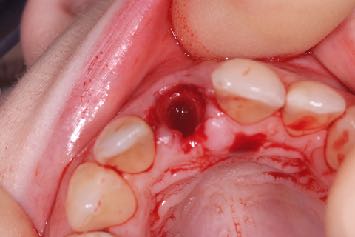

Plus important encore, on lit fréquemment que, pour augmenter artificiellement ce couple, il faudrait pratiquer une plus petite ostéotomie ou recourir à des techniques de compression osseuse. Or on dispose de plusieurs exemples dans la littérature qui prouvent que ces pratiques sont préjudiciables à la cicatrisation, risquent d’endommager l’os et de retarder le processus d’ostéo-intégration.

Il faudrait se concentrer sur la stabilité secondaire et l’obtenir le plus vite possible, en préservant en même temps la viabilité et la stabilité de l’os péri-implantaire, pour assurer la réussite clinique de l'implant à long terme.